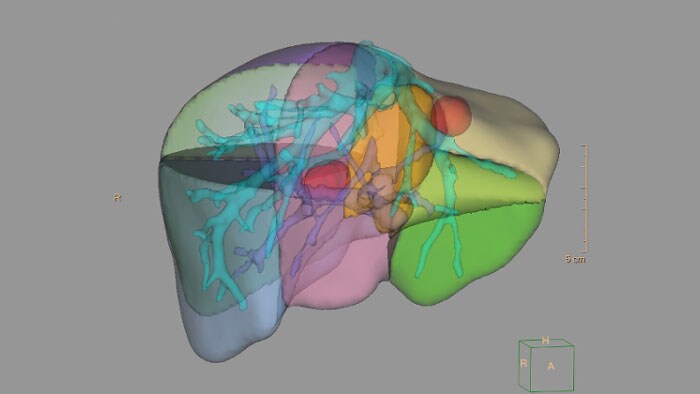

Análise do fígado por TC

Identifica automaticamente o fígado a partir de uma fase venosa portal de um exame trifásico ao fígado. A aplicação fornece ferramentas de segmentação para facilitar o acesso ao fígado, à vasculatura hepática de segmentos vasculares individuais e a lesões identificadas por um médico.